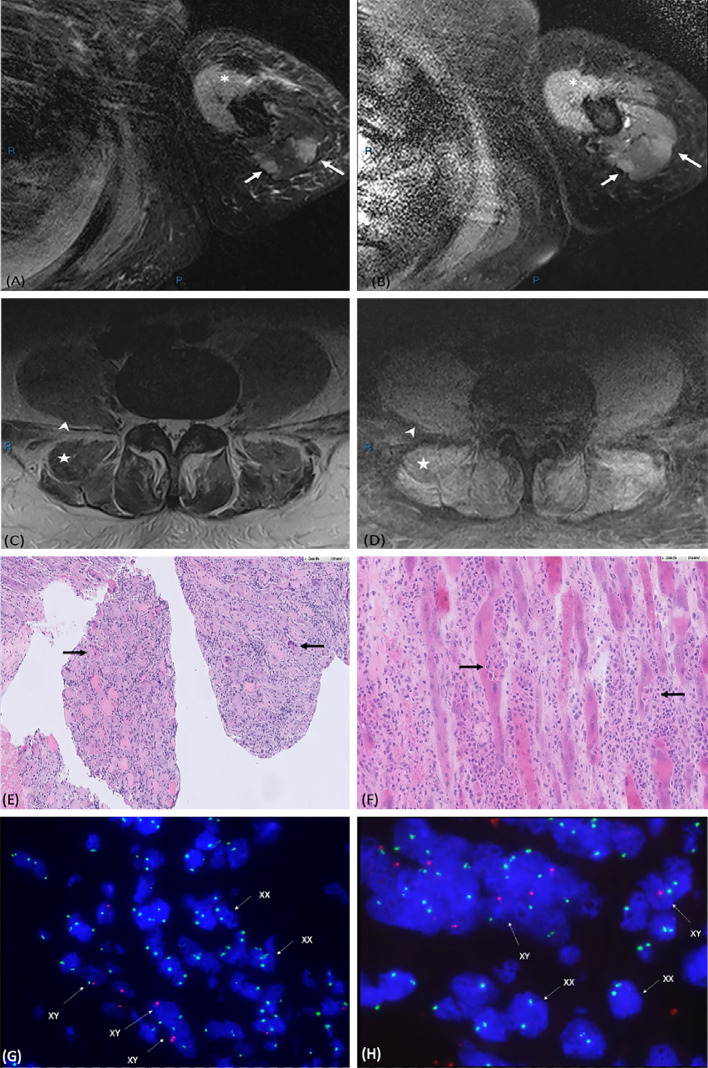

Case report: A 23-year-old man who presented with Philadelphia chromosome (Ph)-positive chronic myeloid leukemia in myeloid blast crisis, underwent HLA-matched sibling (sister) hematopoietic stem cell transplantation. Six months post-transplant, he experienced bilateral arm pain and weakness, with an inability to raise his limbs against gravity. He was also unable to sit erect, and was dyspneic and hypoxic, thus requiring oxygen supplementation. Serum muscle enzyme levels were found to be markedly elevated. Magnetic resonance imaging showed a patchy hyperintense T2-weighted signal and enhancement in the muscle groups of the limbs, as well as in the psoas and erector spinae muscles. The electromyogram results were consistent with those of inflammatory myopathy. Muscle biopsy revealed extensive necrotizing myositis with extensive lymphocyte infiltration throughout the muscle fascicle. Additionally, fluorescence in situ hybridization (FISH) analysis demonstrated that 30% of the nuclei scored were in the muscle fibers of recipient XY origin, and 70% were in T-lymphocytes of donor XX origin. GvHD polymyositis was diagnosed, and the patient responded well to corticosteroids and extracorporeal photopheresis.

Conclusion: GvHD polymyositis can affect various muscle groups and results in various clinical presentations. In our case, truncal involvement resulting in an inability to sit erect was a unique presentation. Prompt diagnosis is important, and we have highlighted a comprehensive multimodal approach, including the potential use of FISH analysis, to aid in diagnosis.